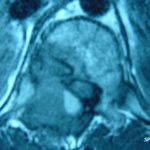

Εικ. 3: Μαγνητική τομογραφία α-στ Οβελιαία (Saggital) λήψη ακολουθία Τ1-Τ2, ζ-ιβ Εγκάρσια (Axial) λήψη ακολουθία Τ1-Τ2

Παρατηρείται ευμεγέθης εξεργασία στα οπίσθια στοιχεία του Θ12 σπονδύλου η οποία προκαλεί διόγκωση των δομών , λέπτυνση του φλοιού, χωρίς σημάδια διάσπασης του φλοιού. Η εξεργασία προβάλλει και στενεύει το σπονδυλικό σωλήνα, ενώ προκαλεί πίεση του νωτιαίου μυελού. Δεν αναγνωρίστηκαν παθολογικά ευρήματα από τον έλεγχο των σπονδυλικών σωμάτων και των μεσοσπονδύλιων τμημάτων της ΟΜΣΣ.